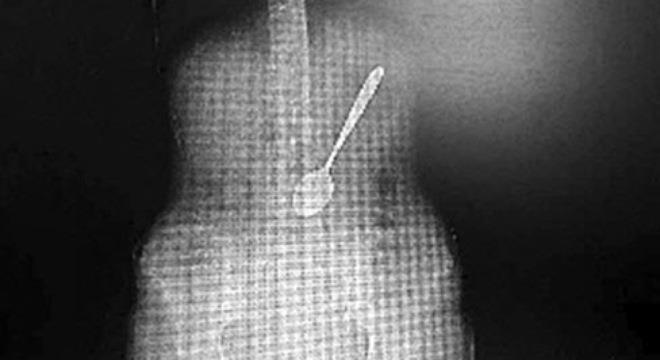

Chiếc thìa dài 13 cm mà bà Lili đã nuốt - Ảnh chụp màn hình. |